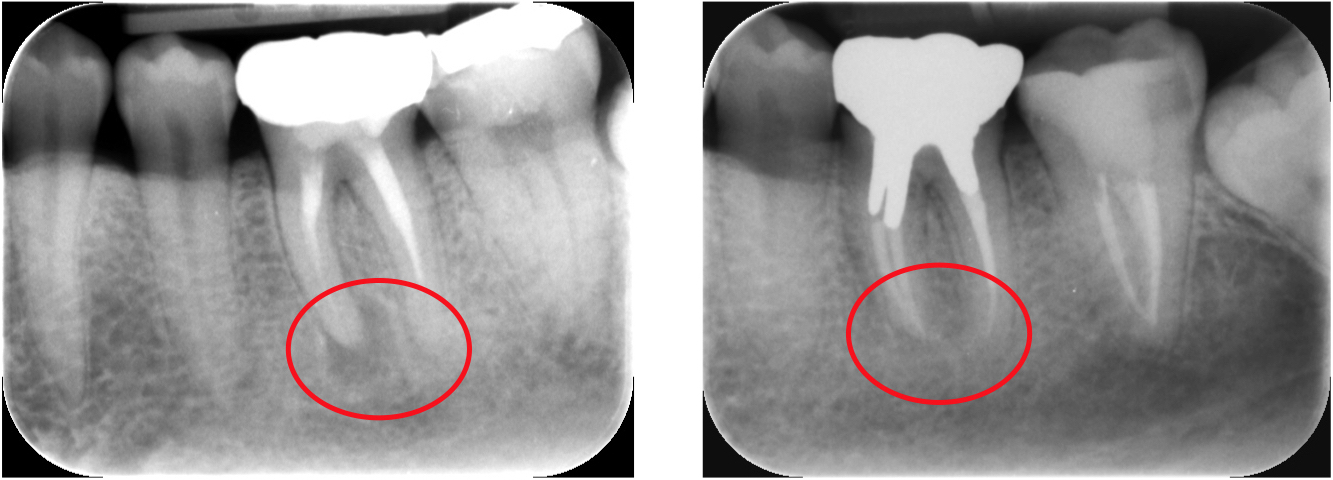

通常の根管治療を行っても症状が良くならない場合には外科的根管治療が必要となってきます。

歯根の外側に感染が及んでいる場合、通常の根管治療では感染源を除去することができないため、感染部位周辺の歯肉から感染源に直接アプローチする必要があります。

感染部周辺の歯肉を切開し、歯根の先端の病変部分を露わにします。

歯槽骨に穴を開け歯の根本から根管治療を行い、感染源を除去します

感染源を除去した後、感染している歯根の先端も取り除きます。

詰物をして歯槽骨の回復を待ち、切開部を縫合して完了です。